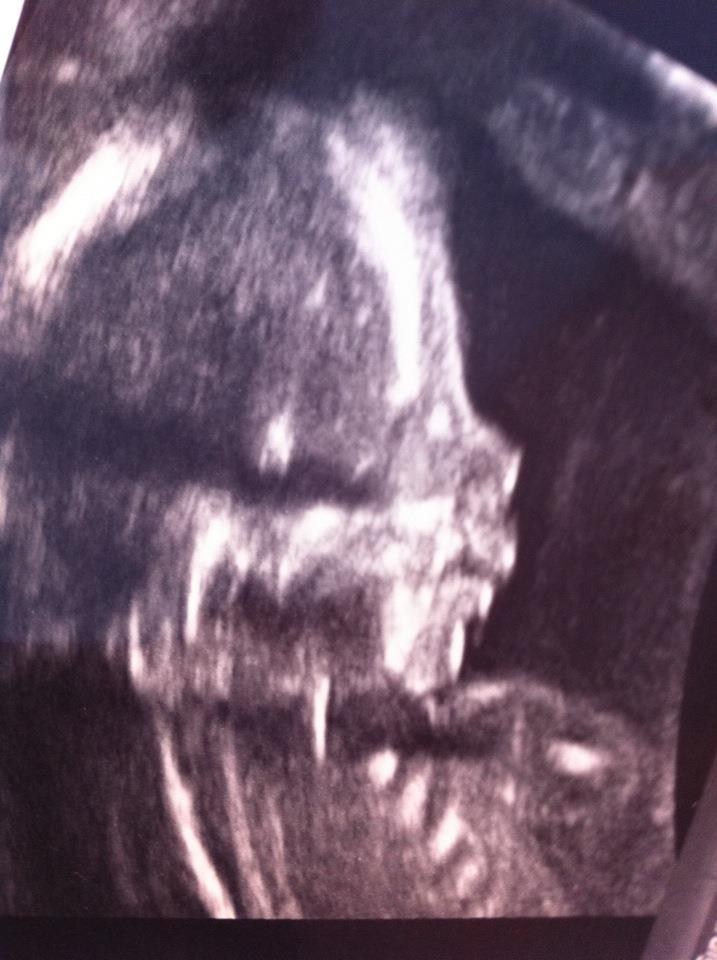

Fik et godt profilbillede og et mindre godt i fuld figur. Han mosler noget rundt efterånden, men bare ikek lige til scanning. Jeg har de sidste par dage flere gange oplevet at det virkelig trykkede nedad og nu fik jeg forklaringen. Han lå under hele scanningen og maste hovedet nedad, som om han tror han skal til at finde vejen ud. Han er nok bare ved at researche, så han er klar når tid er. Han ligner sin mor og så kan han godt lide at være godt forberedt

Det lykkedes til sidst at få gennemgået ham trin for trin og alt ser godt ud og han er vokset helt som normalt. Iihhhh hvor kunne jeg blive liggende på den briks i timevis og bare kigge på ham